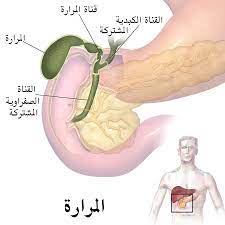

المرارة

.الوصف: كيس صغير يقع تحت الكبد

الوظيفة

.تخزين العصارة الصفراوية التي ينتجها الكبد-

.إفراز العصارة إلى الاثنا عشر عند تناول الدهون لتسهيل هضمها-